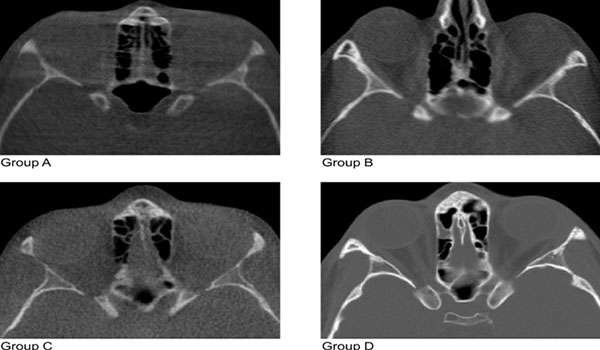

CBCT for CT of bone

CBCT (Cone Beam Computed Tomography) is a specialized type of X-ray equipment used when regular dental or facial X-rays are not sufficient. It uses a cone-shaped X-ray beam to create detailed 3D images of the bone, soft tissues, nerve pathways, and dental structures in a single scan. This technology is particularly useful for evaluating complex cases and planning surgical procedures.